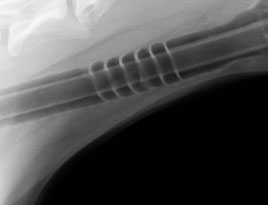

Almost all ET tubes used today depend upon an inflation cuff to seal the tube in the trachea, except the Safe-Seal™ ET tube featuring the Blaine Bafflex System. This new technology uses a series of 6 silicone baffles with carefully engineered pattern and spacing to seal the trachea without pressure points. The flexible baffles allow an “o-ring effect”. The Safe-Seal ET tube lies in the trachea and the sealing baffles touch the tracheal wall leaning towards the larynx. Thus, when the patient inspires the silicone baffles are sucked against the trachea forming a tight seal.